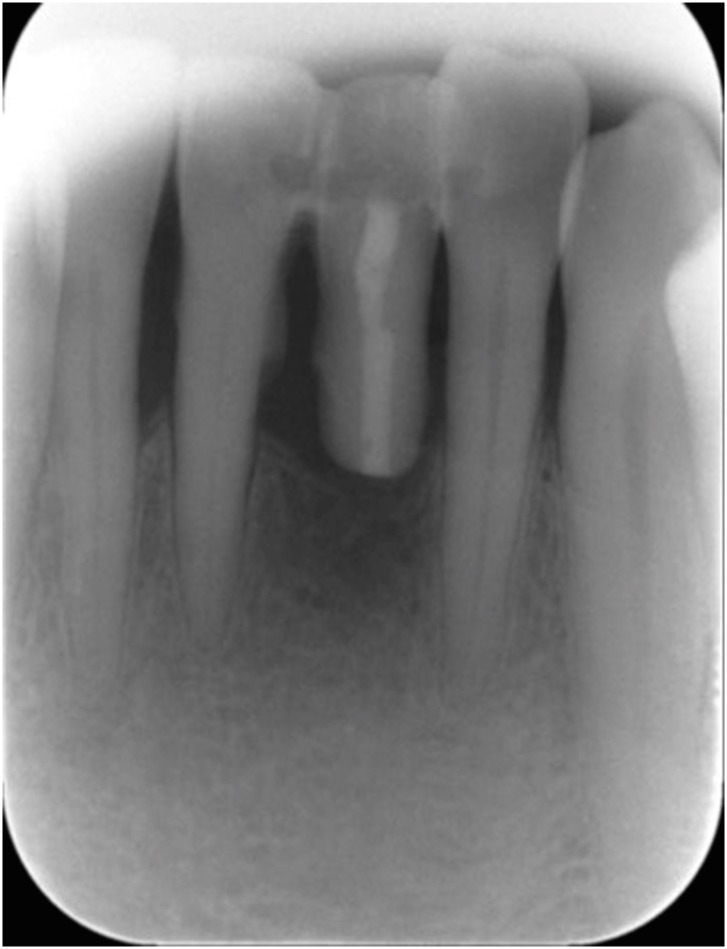

Figure 8

At a 10-month recall check. (A) Intraoral photograph (labial view); (B) intraoral photograph (lingual view); (C) periapical view.

At a 10-month recall examination, the pontic and abutment teeth were in sound condition. No specific discomfort was reported, and the patient was satisfied with having saved his natural tooth. Periapical radiography was taken and it showed bony healing of the extraction socket (Figure 8).